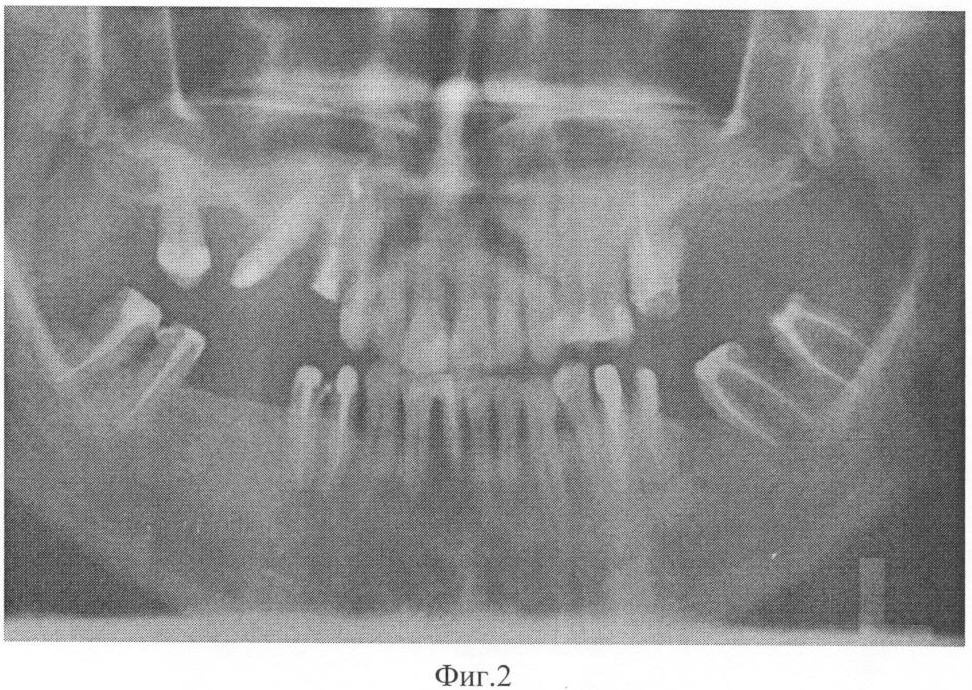

На фиг.2 – рентгенограмма пациента 1 после лечения заявленным способом.

Больному было проведено комплексное лечение, включающее обучение гигиене полости рта, санация некачественно запломбированных каналов, снятие поддесневых зубных отложений и кюретаж пародонтальных карманов, проведение антибиотикотерапии (сумамед 250 мг – 5 дней), удаление 27, 46, гемисекция в области 36, изготовление шинирующих конструкций и временных коронок на нижнюю и верхнюю челюсти. Сразу после проведения хирургического лечения (лоскутная операция с остеопластикой и введением препарата Остеопласт в область вертикальных костных дефектов) был назначен курс препарата Калькохель по одной таблетке три раза в день в течение трех недель, затем препарат Остеохель С по одной таблетке три раза в день в течение трех недель, затем перерыв три недели и повторно те же препараты тем же курсом. Повторное обследование проводили через 11 месяцев после начала лечения. Осмотр полости рта показал следующее: слизистая оболочка десны бледно-розового цвета, без признаков кровоточивости, глубина пародонтальных карманов в пределах 3 мм в области всех зубов. На ортопантомограмме определяется закрытие вертикальных костных дефектов полноценной костной тканью, восстановление формы межзубных перегородок и появление четкой кортикальной пластинки по краю кости.

Сам пациент отмечает значительное улучшение состояния, исчезновение кровоточивости десен и подвижности зубов, отсутствие рецидивов заболевания более 3 лет. Пример подтверждается рентгенограммами, выполненными до лечения – фиг.1 и после лечения – фиг.2.